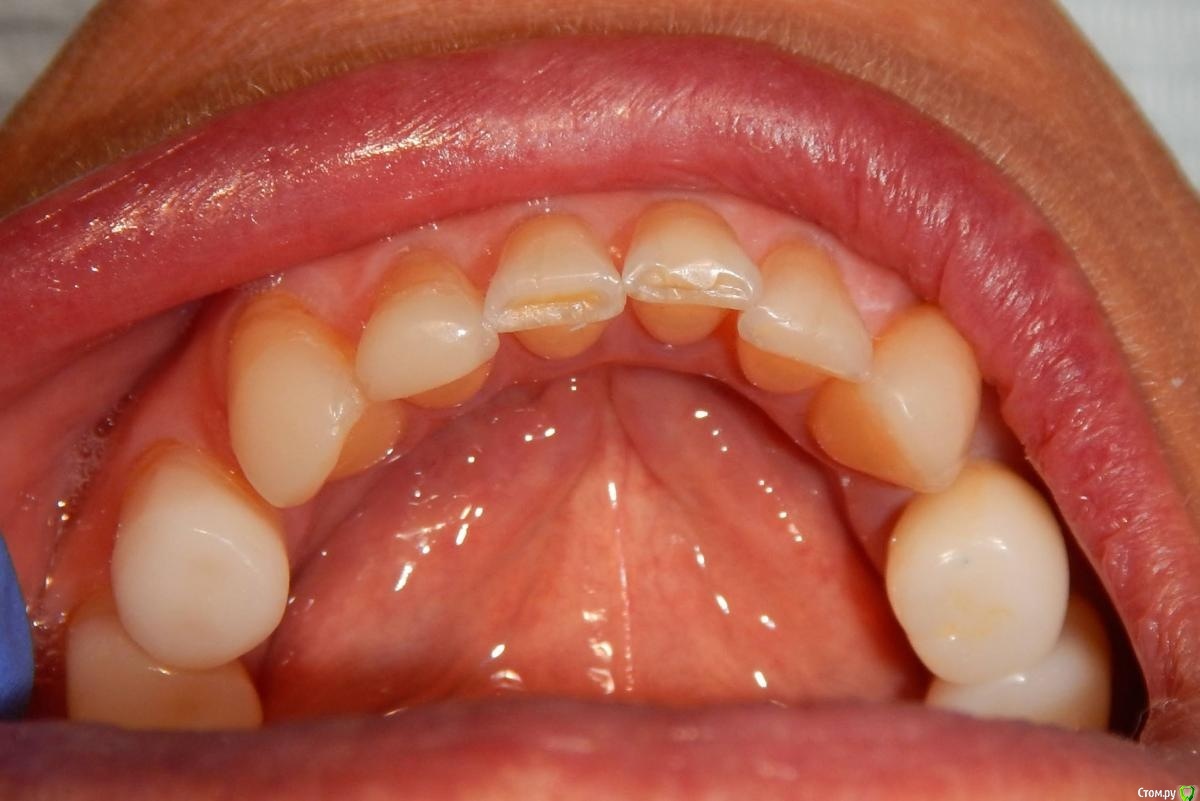

Astronaft Опубликовано 24 января, 2021 Поделиться Опубликовано 24 января, 2021 (изменено) Одиночный цирнокиевый имплантат и расщепление без графта. Пациентка:тонкая хрупкая женщина 55 лет, сконцентрированная на своем здоровье, в некоторой мере мнительная.всегда тяжелые заживления после удалений (по опросам)есть результаты Клиффорд теста (такая книжка под 200 страниц с in vitro аллерго-пробами на все известные материалы) Поставленная цель:только цирконий Мне было интересно найти вариант найболее приемленый пациентке и мне. С минимом хирургического риска и риском сожаления пациентки про выбор костного материала. Во-первых, я не использую аллографты - философски, чужие протеины, неприятный запах - просто основываясь на своем мнении.Во-вторых, мнительные пациенты склонны "пойти и почитать" до или потом и как следствие внушить себе вещи которых может и не было. Но по скольку мысль материальна... Все обсудил заранее.План: ридж сплит (расщепление), имплантат без графта, свободный СТ графт; если случается вестибулярная рецессия - пилим зирконий во рту. Ридж сплит сделан пьезотомом - крестальный и вертикальные пропилы на глубины около 8-10мм.Пилотное сверло.Развдвинул кость остеотомами от 1.6мм до 3.5мм в диаметре.Очень мягкая кость - напомнила мегкую максиллу плотности ногтевой пластинки вестибулярно.Имплант встал легко, но торк 40нсм. СТ графт из области 18. Деэпителизирую скальпелем уже потом. Тут интересно отметить, что я перестал боятся ошметков эпителия.Пончо сверху имплантата (а-ля шашлык Карлоса).Швы. PTFE всегда хорош. 12 недель.Красивая десна.Периотест -5.8 - отличный результат.Оттиск. Циркониевая коронка симметричная другой стороне. Изменено 24 января, 2021 пользователем Astronaft 19 Ссылка на комментарий

Astronaft Опубликовано 25 января, 2021 Автор Поделиться Опубликовано 25 января, 2021 Спасибо.День операции, 12 недель, день цементировки. 3 1 Ссылка на комментарий